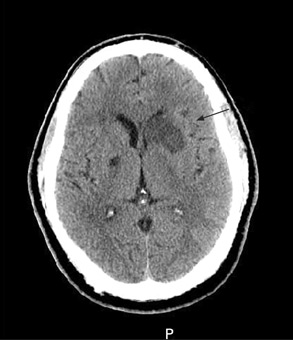

tomografia computadorizada (TC) do crânio

Solicite imagens cerebrais tão logo quanto possível (no máximo 1 hora após a chegada ao hospital).[64] A TC de crânio sem contraste é a investigação de escolha no AVC agudo.

Use a tomografia computadorizada para diferenciar entre AVC isquêmico e AVC hemorrágico; o que deve ser feito antes de se iniciar a trombólise no AVC isquêmico e antes de se reverter a anticoagulação na hemorragia intracerebral induzida por anticoagulação.[64]

Lembre-se de que o AVC isquêmico é um diagnóstico clínico baseado em sinais e sintomas; uma tomografia computadorizada normal não descarta um AVC - particularmente nas primeiras horas, a tomografia computadorizada pode estar normal ou mostrar alterações isquêmicas muito sutis. É extremamente provável que uma ressonância magnética (RM) na presença de sintomas continuados mostre o AVC. Uma ressonância magnética ponderada por difusão normal é muito improvável se o paciente tiver sofrido um AVC.[85]

[Figure caption and citation for the preceding image starts]: Tomografia computadorizada (TC) de crânio sem contraste mostrando infarto ganglionar basal isolado esquerdo subagudo com efeito de massa protuberante frontal esquerdaCortesia do BMJ Case Reports 2009; (doi:10.1136/bcr.10.2008.1139) [Citation ends].